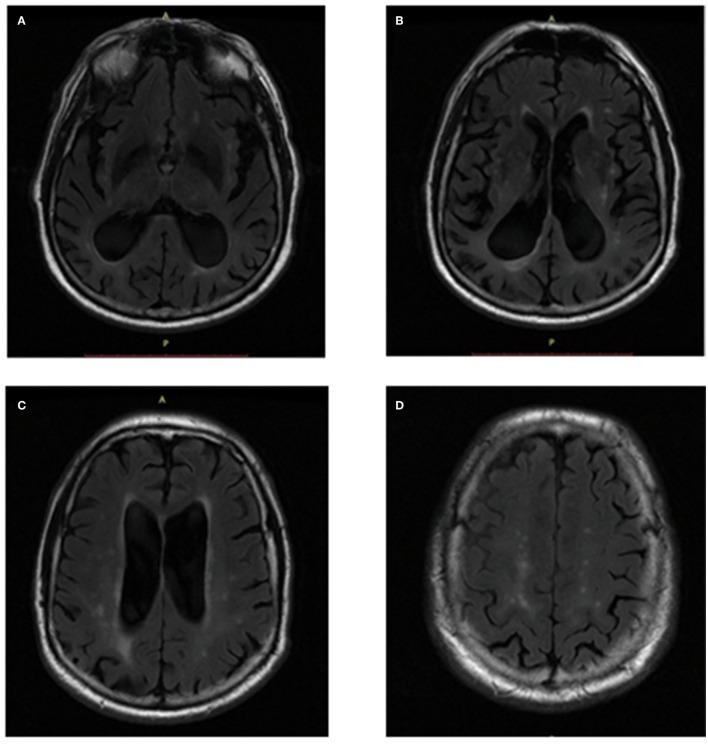

阿尔茨海默病患者白质高信号负荷与脑区容积测定之间的相关性

The Correlation Between White Matter Hyperintensity Burden and Regional Brain Volumetry in Patients With Alzheimer's Disease.

White matter hyperintensities (WMHs) and regional brain lobe atrophy coexist in the brain of patients with Alzheimer's disease (AD), but the association between them in patients with AD still lacks comprehensive investigation and solid imaging data support.

OBJECTIVE

We explored whether WMHs can promote the pathological process of AD by aggravating atrophy in specific brain regions and tried to explain the regional specificity of these relationships.

A sample of 240 adults including 180 normal controls (NCs) and 80 cases with AD were drawn from the ADNI database. T1-weighted magnetic resonance imaging (MRI) and T2-weighted fluid-attenuated MRI of the participants were downloaded and were analyzed using AccuBrain to generate the quantitative ratio of WMHs (WMHr, WMH volumes corrected by intracranial volume) and regional brain atrophy. We also divided WMHr into periventricular WMHr (PVWMHr) and deep WMHr (DWMHr) for the purpose of this study. The Cholinergic Pathways Hyperintensities Scale (CHIPS) scores were conducted by two evaluators. Independent -test, Mann-Whitney test, or χ test were used to compare the demographic characteristics, and Spearman correlation coefficient values were used to determine the association between WMHs and different regions of brain atrophy.

Positive association between WMHr and quantitative medial temporal lobe atrophy (QMTA) ( = 0.281, = 0.011), temporal lobe atrophy ( = 0.285, = 0.011), and insular atrophy ( = 0.406, < 0.001) was found in the AD group before Bonferroni correction. PVWMHr contributed to these correlations. By separately analyzing the relationship between PVWMHr and brain atrophy, we found that there were still positive correlations after correction in QMTA ( = 0.325, = 0.003), temporal lobe atrophy ( = 0.298, = 0.007), and insular atrophy ( = 0.429, < 0.001) in AD group.

WMH severity tends to be associated with regional brain atrophy in patients with AD, especially with medial temporal lobe, temporal lobe, and insular lobe atrophy. PVWMHs were devoted to these correlations.